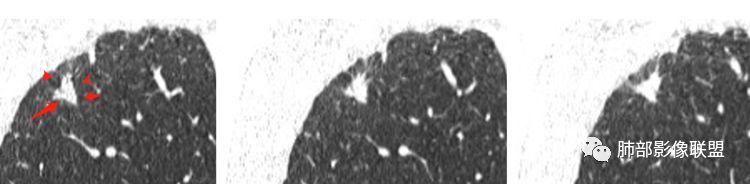

笨丫头:右上肺结节,有分叶,毛刺,胸膜牵拉,空泡影,考虑恶性,腺癌杨泽锋:尖段实性结节,边缘平直、长毛刺、支气管壁增粗、中近段未见截断,首先考虑炎性结节,因为没有树丫征,诊断结核信心不足小梅:43岁男性,无呼吸道症状,无畏寒发热,右肺上叶尖段胸膜下不规则实性结节,周围无磨玻璃影,有胸膜牵拉有一定的收缩力,结节周边以凹陷平直为主,没有见到明星卫星灶。结节内部的低密度要区别小支气管和空泡证,首先考虑炎性,结核可能性大。把肿瘤往后放待鉴别

刘丹:右肺尖结节,胸膜牵拉线清晰,考虑结核,鉴别腺癌。紫气东来:右肺上叶结节,长毛刺,边缘平直,血管增粗,胸膜牵拉,考虑炎性结节,鉴别腺凝睦:右肺上叶不规则实性结节,边缘长毛刺,周围支气管壁增厚,考虑结核。薏米:右肺上叶结节,有毛刺,胸膜牵拉,空泡,考虑腺癌,鉴别炎性结节清嘉:不规则类结节,边缘有平直内凹,清秀胸膜线,考虑良性病变可能大,结核?看图说话:实性结节,边缘平直、部分膨隆,长毛刺、支气管壁增粗未见截断,首先考虑炎性结节,建议复查除外腺癌市医院--时建文:右上肺结节,有分叶,毛刺,胸膜牵拉,空泡影,腺癌?甄德强:实性结节,边缘纤细长毛刺,支气管壁增厚,似乎有卫星病灶,考虑良性病例结核,不除外类风湿结节。似水流年(陆喜红 ) :右肺上叶不规则实性结节,边缘清楚,边缘长毛刺,邻近胸膜凹陷,病灶周围无卫星灶,病灶内部见低点空气密度影(空泡或者伴支气管管壁增厚),考虑炎性结节(这个人白细胞和中性粒细胞高,应该是有急性感染性疾病 只是肺部的结节偏慢性的,这个结节应该跟膝关节反复痛有关系吧?),普通炎性结节?类风湿性关节炎相关?小兜:晨读,青年男性,关节疼痛两年,再发三天。右肺上叶不规则结节,边缘细长毛刺,胸膜牵拉,支气管壁增厚,考虑为良性病变,类风湿结节或者结核可能马春平(张家港市一院胸外科):金鱼眼、长毛刺、小结节中低密度,细支气管畸形肉芽肿>结核肉芽肿崔少钢:右肺上叶病变,平直内收为主,毛刺偏长,见胸膜牵拉,白细胞高,肿瘤标志物正常,考虑炎性病变,需排除类风湿引起的肺内改变。丽:中年男性,右肺上叶结节,重建呈不规则形,边缘平直多发长毛刺较软,并可见胸膜牵拉,内可见支气管影,无扩张,首先考虑良性,炎性结节可能大,结合关节疼痛病史,类风湿结节待排红星:中年男性,以关节疼痛为首发症状,检查发现右上肺叶实性结节,明显分叶及长索状影,邻近胸膜面增厚,结节内支气管扩张。患者白细胞明显升高,估计与关节有关,考虑结核肉芽肿?腺癌也有可能,需排除玫:右肺上叶结节,边缘见分叶及长短不一毛刺,胸膜牵拉,病灶内见小空泡影,类风湿病史,实验室检查部分血项增高,考虑炎性病变可能,不除外腺癌。Lotus:先考虑炎性,警惕恶性吧,感觉关键在于支气管壁厚的权重和病灶本身的形态闫美利:中年男性,右肺上叶不规则结节,长短毛刺,边缘平直收缩,胸膜牵拉,考虑炎性结节,鉴别腺癌张小兵:右肺上叶尖段不规则实性结节,边缘收缩平直凹陷,胸膜牵拉线清秀,内见裂隙样低密度,周围见卫星灶,炎性结节,慢性结核结节可能。小飞:右肺上叶实性结节,边缘平直、收缩为主,可见长毛刺、胸膜牵拉,考虑炎性病灶可能性大傅昌瑜:青年男性,关节疼痛两年,再发三天,加重1天。血白细胞升高。右肺上叶尖段结节,边缘细长毛刺,胸膜牵拉线清秀、纤细,支气管壁增厚,考虑为良性病变,周围有小点状结节,考虑结核可能性大。结节局部似有膨隆,腺癌待排。红日东升:中年男性,右肺上叶不规则结节,形态平直、凹陷,边缘细长清秀毛刺,未见清楚GGO,邻近胸膜下有小斑片,考虑为炎性病变徐婕:尖段实性结节,边缘平直、长毛刺、支气管壁增粗、中近段未见截断,首先考虑炎性结节?????天涯?????:结节周围细长毛刺,小空洞内壁光滑,关节痛,结核?鉴别类风湿、腺~波波:右肺上叶结节,长毛刺,边缘平直凹陷,膨胀性不够,胸膜牵拉及血管集束,考虑结核结节,鉴别腺癌。水晶石头:患者中年男性,有反复关节疼痛,短期加重(考虑存在反复使用激素药物可能)。查血常规白细胞计数及中性粒细胞百分比升高。肿瘤标志物正常。胸部CT:右肺上叶尖段不规则实性结节,边缘清楚,可见分叶、长毛刺及胸膜牵拉征象,病灶周围无明显卫星灶,病灶内见支气管壁增厚,牵拉扩张支气管,综合考虑良性病变,结核结节可能性大,鉴别鳞癌及腺癌可能。巴伟:右肺上叶结节,病灶较散,边缘平直为主,细长毛刺,清秀胸膜牵拉线,首先考虑炎性结节,鉴别腺癌金惠:中年男性,右上肺结节,外周分叶,毛刺,肿瘤可能性大,但关节疼痛2年,不排除风湿性结节彭君:右上肺结节 边缘局部膨隆 边缘见少许磨玻璃边界清 周围长索条 邻近胸膜肥厚 首先考虑腺癌 鉴别结核joyzhy:右上肺结节,收缩,长毛刺,缺乏磨玻璃,考虑炎性结节,结核?毛勤香:右肺上叶尖段结节,边缘平直收缩为主,邻近支气管壁稍增厚,邻近牵拉胸膜线清秀,邻近胸膜稍增厚,考虑良性,结核可能性大,有关节炎病史,不典型类风湿结节不除外。王仁杰:患者中年男性,反复关节疼痛,短期加重,血常规白细胞计数及中性粒细胞百分比升高,肿瘤标志物正常。胸部CT:右肺上叶尖段不规则实性结节,边缘清楚,可见分叶、长毛刺及胸膜牵拉征象,病灶周围无明显卫星灶,综合考虑良性病变,建议抗炎治疗后复查。Zhuweichao:右肺上叶结节,长毛刺,边缘平直,考虑炎性,胸膜牵拉不放心,鉴别腺三个石头:右肺上叶不规则结节,平直,收缩,长毛刺,胸膜牵拉,考虑炎性。弹指之间:右肺上叶不规则结节,见空泡,边缘长毛刺,有收缩感,胸膜牵拉,考虑炎性肉芽肿性病变>细支气管畸形。李:右肺上叶不规则结节,分叶,空泡,提示恶性,考虑腺tsing(青):晨读:右肺上叶结节,形态不规则,内似见空泡,边缘长短不一毛刺,临近胸膜牵拉,体检发现,无对应症状,慢性炎症?李忠敏 274:右肺上叶不规则结节,边缘平直凹陷,多发长毛刺,临近胸膜牵拉,考虑良性病变,慢性炎症?类风湿结节?内见空泡腺也需鉴别!飞:患者中年男性。胸部CT:右肺上叶尖段不规则实性结节,边缘清楚,可见分叶、毛刺并胸膜牵拉征象,病灶周围无明显卫星灶,病灶内可见牵空泡征,实验室指标指标虽不指向恶性,但影像学不排除腺癌可能,建议抗炎后复查。

首先病灶是实性?还是GGN?实性我们就按实性的思路走。密度均匀;

支气管通畅吧。

形态如何?三角形

边缘整体U型凹陷、平直

边缘长索条

不踏实的地方就是内部支气管部分区域不规整

我考虑炎性放前面,恶性待排,定期复查。这我是按写报告的思路去分析。一些特殊炎症就不一定,例如结核,也就是说结核不能除外,结核也是炎性病变,特殊感染而已。